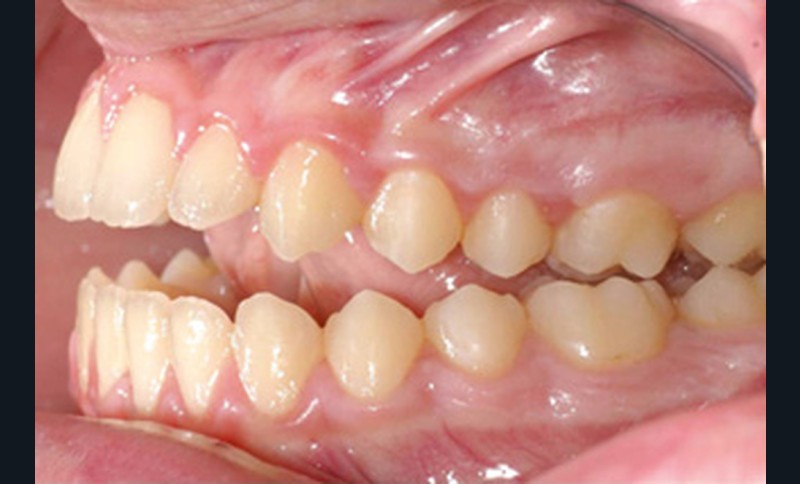

Cette patiente a été suivie dans le cadre d’un traitement interceptif alors qu’elle avait 9 ans. Elle présentait une endognathie maxillaire et une béance antérieure importante liées à des troubles fonctionnels évidents. En effet, l’examen clinique révélait une ventilation buccale exclusive, des ronflements nocturnes et une déglutition atypique. Nous avions noté à l’époque un manque de place pour l’évolution des dents définitives et un inversé d’articulé bilatéral. Les parents avaient rencontré un médecin ORL, mais avaient refusé une intervention visant à enlever les amygdales. Les deux canines maxillaires étaient incluses (fig. 1 à 6).

Quelques années plus tard, au moment de démarrer sa prise en charge orthodontique, la patiente présentait à nouveau une béance antérieure, un décalage des milieux incisifs de 2 mm et le problème transversal avait récidivé. Lors de l’examen clinique, elle présentait un inversé d’occlusion bilatéral postérieur et une ventilation buccale exclusive. À la suite du refus de réaliser l’amygdalectomie de façon précoce, elle ronflait toujours et sa déglutition ne s’était pas modifiée malgré des séances d’orthophonie (fig. 7 à 15).